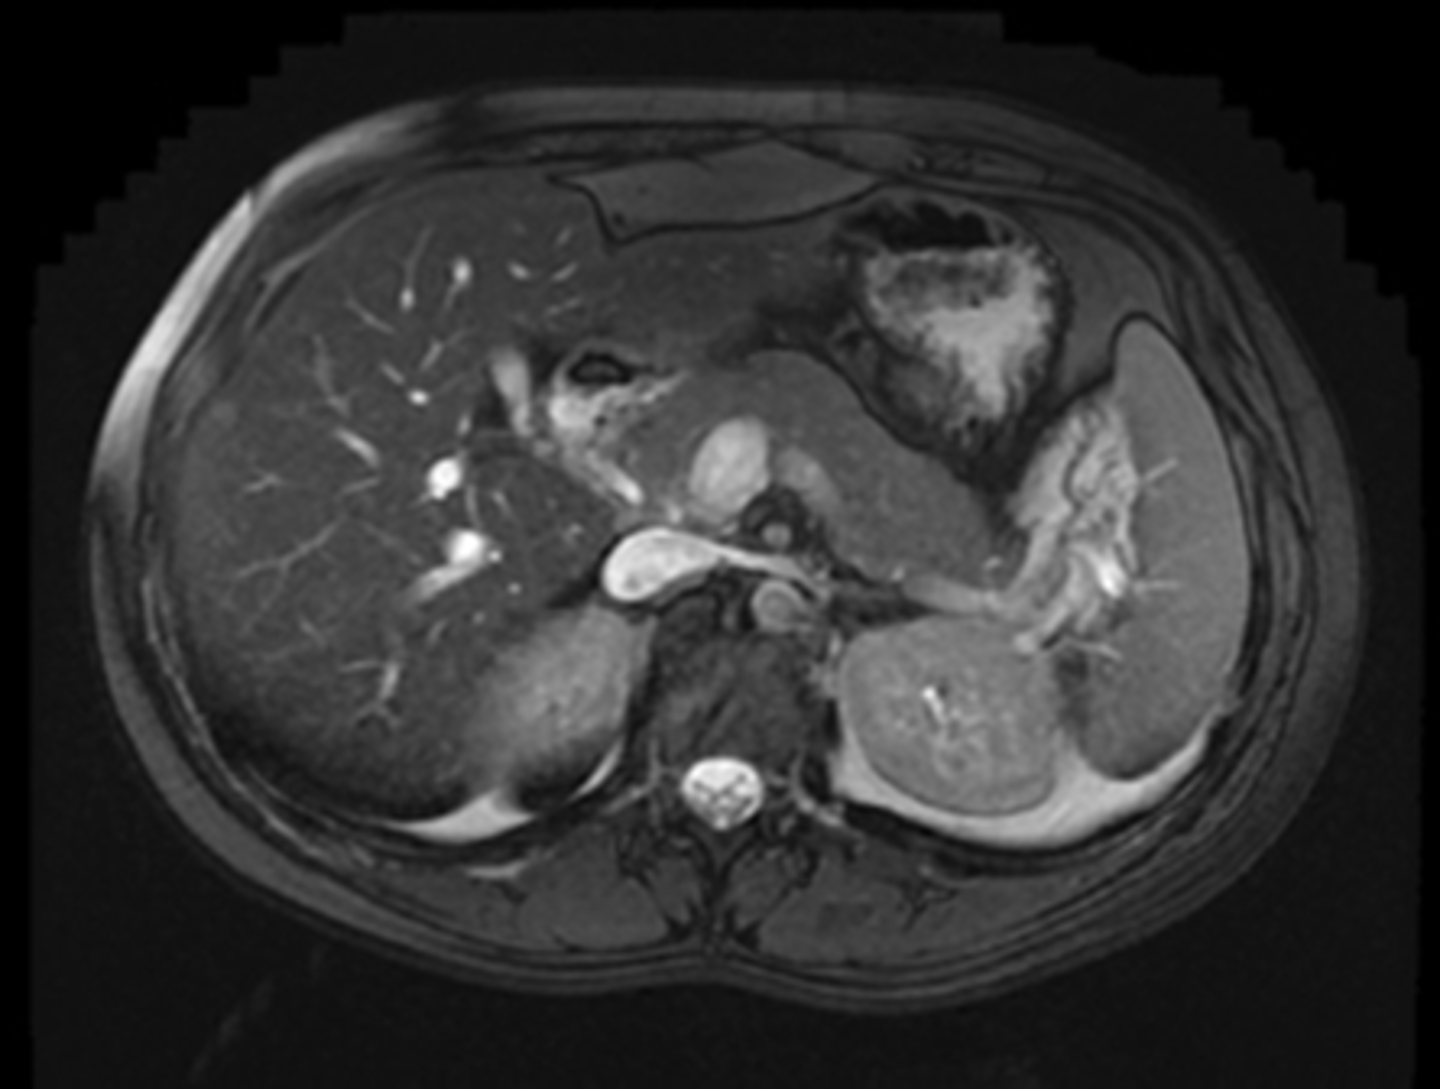

NORMAL LIVER ANATOMY

DOTTED BLACK ARROW:

Ligamentum teres - divides the left love of the liver into medial and latera segments, with larger right lobe more posterior.

M: Medial segment of left lobe

L: Lateral segment of left lobe

R: larger right lobe of liver.

PV: Portal vein, lying just posterior to the hepatic artery

SOLID BLACK ARROW: hepatic artery

SOLID WHITE ARROW: Splenic artery, follows the path of the pancreas towards the spleen

P: PANCREAS

S: Spleen

IVC: Inferior vena cava, lying right of the aorta

A: Aorta